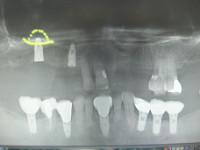

5/28日施術分オペ画像

この画像も5月28日施術分のオペ画像になります。

この症例は右上3番が歯根破折の為に保存不可能な状態になり尚且つ入れ歯の鉤歯であったが為に、入れ歯の保持が厳しくなり来院された患者様でした、。

すでに下顎には複数本のインプラントを埋入され快調にご使用されているとのことで、上顎にもインプラントによる義歯固定の治療を希望されましたので3番相当部は抜歯即時で埋入し6番相当部にはソケットリフト法を併用しましてインプラントを問題なく埋入いたしました。